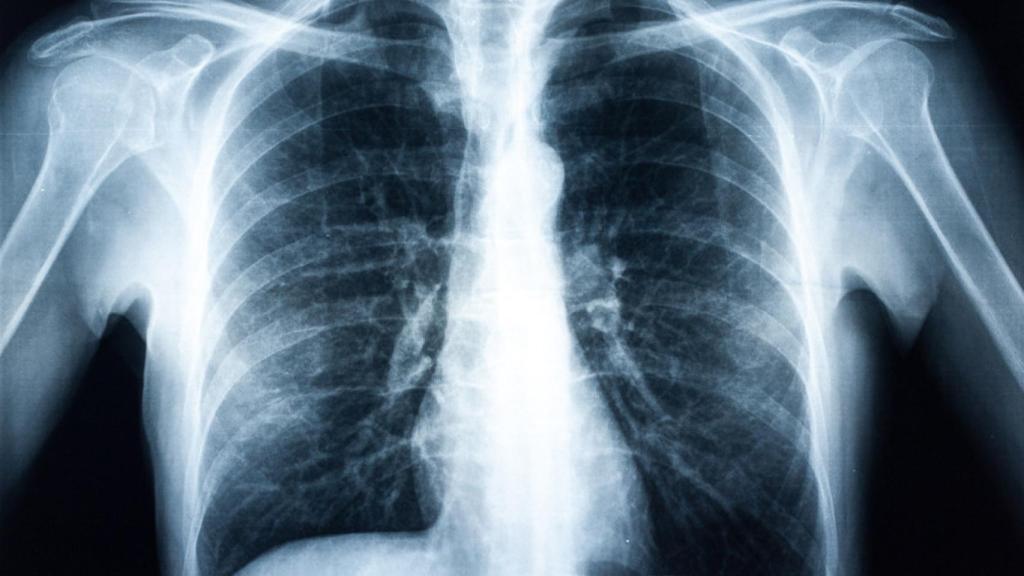

El dispositivo ha sido entrenado con un total de 108.948 imágenes de rayos x de tórax correspondientes a 32.717 pacientes. El tiempo de procesado por radiografía es inferior a un minuto y permite la generación de colas de trabajo de manera simultánea por múltiples usuarios.

Esta herramienta de Medicina de Precisión es capaz ya de facilitar a los radiólogos detectar si un paciente posee masa tumoral con una precisión del 92% y ofrecer el diagnóstico al radiólogo en menos de 1 minuto. El prototipo ha sido entrenado para cáncer de pulmón y cáncer de mama. Además, ha sido validado por un comité ético.

Pulmones en una radiografía.